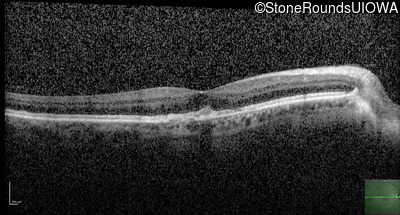

Optical Coherence Tomography - Left - 20/40 +1

Exemplar / OCT Stack